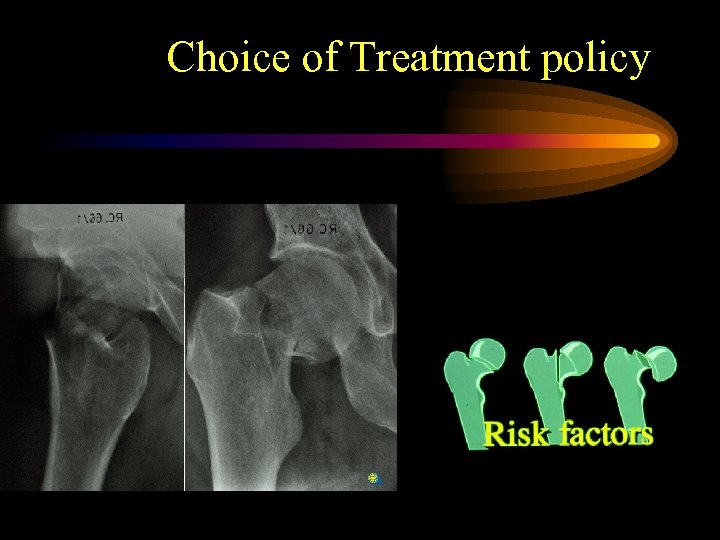

Choice of Treatment policy

Choice of Treatment policy

Fracture related pattern of femoral neck fractures representing risk for osteofixation failure, non-union and avascular necrosis • Grade of dislocation (Garden 1972, Thorngren 1991) • Size of head fragment (Benterud et al. Acta Orth Scand 1994) • Posterior comminution (Benterud et al. 1997) • Osteoporosis (Bentley 1972, Riska 1969, Anderson 1969, Thorngren 1995)

Fracture related pattern of femoral neck fractures representing risk for osteofixation failure, non-union and avascular necrosis • Grade of dislocation (Garden 1972, Thorngren 1991) • Size of head fragment (Benterud et al. Acta Orth Scand 1994) • Posterior comminution (Benterud et al. 1997) • Osteoporosis (Bentley 1972, Riska 1969, Anderson 1969, Thorngren 1995)

Fracture related pattern of femoral neck fractures leading to a “treatment policy”. . • Impacted fractures are reported to have less incidence of non-unions (Bentley G, JBJS; 50 B: 551, 1968, Raymakers, 1993) • Impacted fractures develop less segmental collapse in avascular necrosis of the head ? Crawford reported 12 % of avascular necrosis in 50 impacted fractures out of 339 femoral neck fractures with an overall incidence of avascular necrosis in 37% (Crawford H, JBJS; 47 A: 830, 1965)

Fracture related pattern of femoral neck fractures leading to a “treatment policy”. . • Impacted fractures are reported to have less incidence of non-unions (Bentley G, JBJS; 50 B: 551, 1968, Raymakers, 1993) • Impacted fractures develop less segmental collapse in avascular necrosis of the head ? Crawford reported 12 % of avascular necrosis in 50 impacted fractures out of 339 femoral neck fractures with an overall incidence of avascular necrosis in 37% (Crawford H, JBJS; 47 A: 830, 1965)